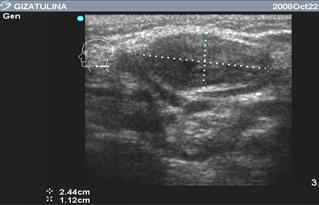

Представляется интересным динамическое эхографическое исследование. Ниже представлена эхографическая картина острого гнойного лимфаденита у девочки Г. трёх лет. На рис. 6 (А) представлена картина острого гнойного лимфаденита в день поступления.

Эхограмма этой же больной через три дня после вскрытия и дренирования гнойника (рис. 6.Б), обращает уменьшение размеров участка гнойного расплавления, отсутствие гнойного затека. Что говорит об эффективности лечения. На следующем рисунке (рис. 7), представлена эхограмма этой же пациентки, выполненная на 11 сутки, с практически восстановленной структурой лимфоузла.

Таким образом, благодаря эхографическому исследованию можно выявить стадию гнойного расплавления, точно локализовать процесс, проследить динамику и предупредить возможные осложнения. Также метод позволяет проследить результат лечения после хирургического вмешательства.

Рис. 6. Эхограмма острого гнойного лимфаденита

(маркерами и стрелкой обозначена зона гнойного расплавления)